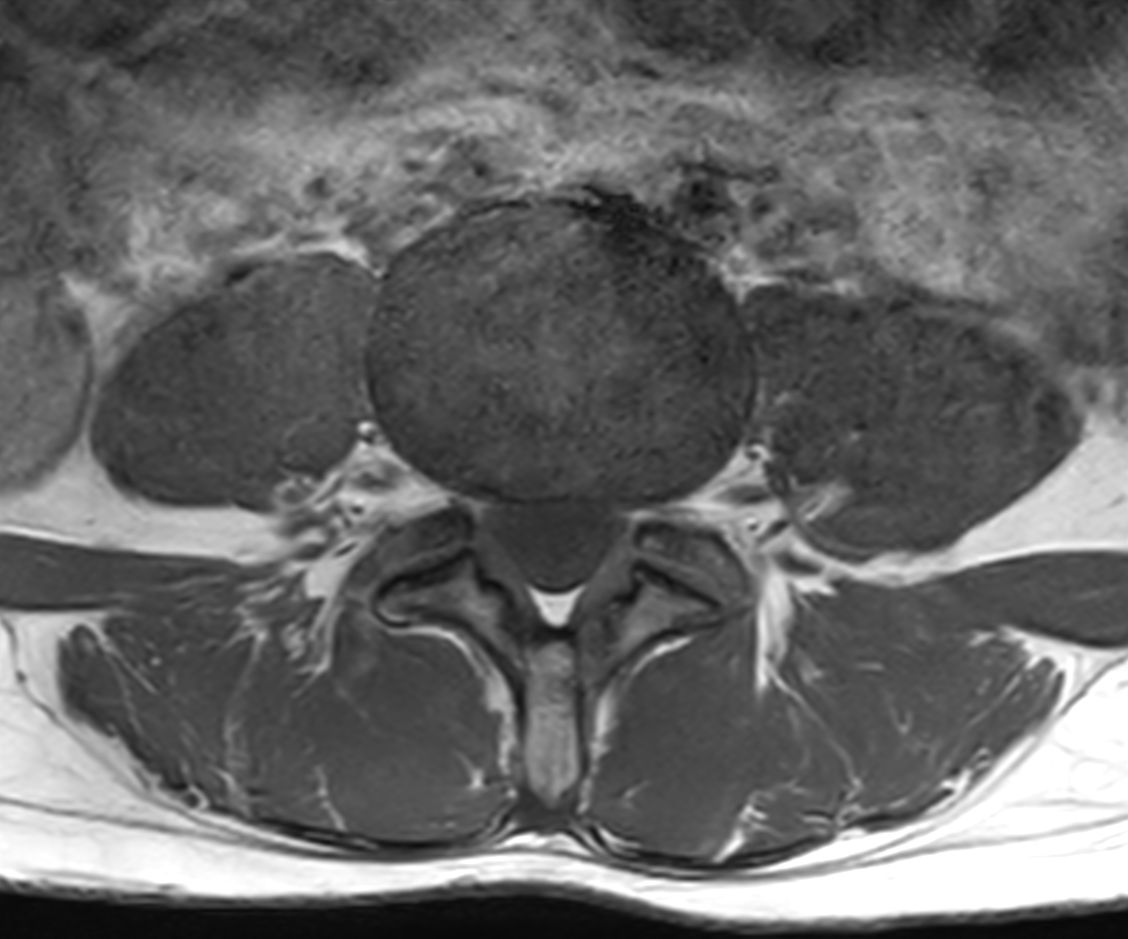

Axial T2w TSE

Axial T1w TSE